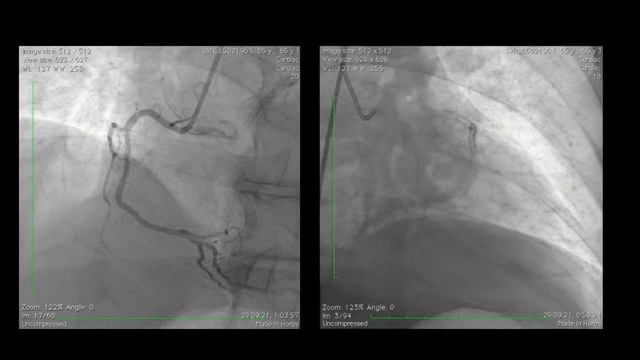

Скрыпник Д.В. Технические аспекты тромбоэкстракции при дистальных окклюзиях у пациентов с ИИ

1.10.2021 Московский курс по сосудистой патологии Дистальные окклюзии артерий головного мозга у пациентов с ишемическим инсультом автор видео Сверхъестественное экономическое эзотерическое знание загруж...